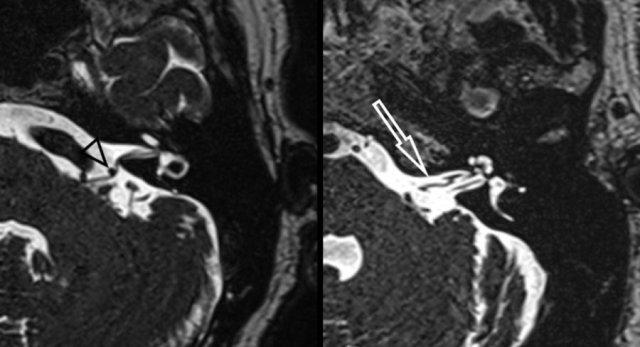

Hình ảnh CISS T2W nặng bên trái cho thấy xung đột thần kinh-mạch máu của động mạch tiểu não sau dưới với sự chèn ép và di lệch dây thần kinh mặt và dây thần kinh tiền đình-ốc tai (hình bên trái, đầu mũi tên đen).

Hình bên phải cho thấy vòng mạch độ 3 (>50%) của động mạch tiểu não trước dưới trong ống tai trong bên trái (mũi tên trắng).